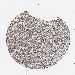

KIDNEY RENAL CLEAR CELL CARCINOMA (TCGA) - Interactive survival scatter ploti

The Survival Scatter plot shows the clinical status (i.e. dead or alive) for all individuals in the patient cohort, based on the same data that underlies the corresponding Kaplan-Meier plots. Patients that are alive at last time for follow-up are shown in blue and patients who have died during the study are shown in red.

The x-axis shows the expression levels (FPKM) of the investigated gene in the tumor tissue at the time of diagnosis. The y-axis shows the follow-up time after diagnosis (years). Both axes are complimented with kernel density curves demonstrating the data density over the axes. The top density plot shows the expression levels (FPKM) distribution among dead (red) and alive patients (blue). The right density plot shows the data density of the survived years of dead patients with high and low expression levels respectively, stratified using the cutoff indicated by the vertical dashed line through the Survival Scatter plot. This cutoff is automatically defined based on the FPKM cutoff that minimizes the p-score. The cutoff can be changed by dragging the vertical line or by entering a cutoff value in the square labeled "Current cut-off".

Under the Survival Scatter plot the p-score landscape (black curve; left axis) is shown together with dead median separation (red curve; right axis). Dead median separation is the difference in median mRNA expression between patients who have died with high and low expression, respectively. It is calculated as follows: median FPKM expression of dead patients with high expression - median FPKM expression of dead patients with low expression. This is intended to aid the user in visually exploring custom cutoffs and the associated p-scores and dead median separation.

Individual patient data is displayed and can be filtered by clicking on one or more of the category buttons on the top of the page. Categories describing expression level and patient information include: high, low, alive, dead, female, male and tumor stages. The scale of the x-axis can be toggled between linear and log-scale by clicking on the "x log" button. Mouse-over function shows TCGA ID, patient information and mRNA expression (FPKM) for each patient.

& Survival analysisi

Kaplan-Meier plots summarize results from analysis of correlation between mRNA expression level and patient survival. Patients were divided based on level of expression into one of the two groups "low" (under cut off) or "high" (over cut off). X-axis shows time for survival (years) and y-axis shows the probability of survival, where 1.0 corresponds to 100 percent.

KIF21A is potential prognostic, high expression is favorable in Kidney Renal Clear Cell Carcinoma (TCGA)

Best expression cut offi

Based on the FPKM value of each gene, patients were classified into two groups and association between prognosis (survival) and gene expression (FPKM) was examined. The best expression cut-off refers the FPKM value that yields maximal difference with regard to survival between the two groups at the lowest log-rank P-value. Best expression cut-off was selected based on survival analysis .

When clicking on this number, the vertical dashed line indicating cut-off, the interactive survival plot, and the Kaplan-Meier curve will be adjusted to show results based on the best expression cut-off.

: 10.38

TCGA RNA samplesi

RNA-seq data is reported as average FPKM (number Fragments Per Kilobase of exon per Million reads), generated by the The Cancer Genome Atlas (TCGA) .

Normal distribution across the dataset is visualized with box plots, shown as median and 25th and 75th percentiles. Points are displayed as outliers if they are above or below 1.5 times the interquartile range. FPKM values of the individual samples are presented next to the box plot.

Average pTPM 17.2

Number of samples 521